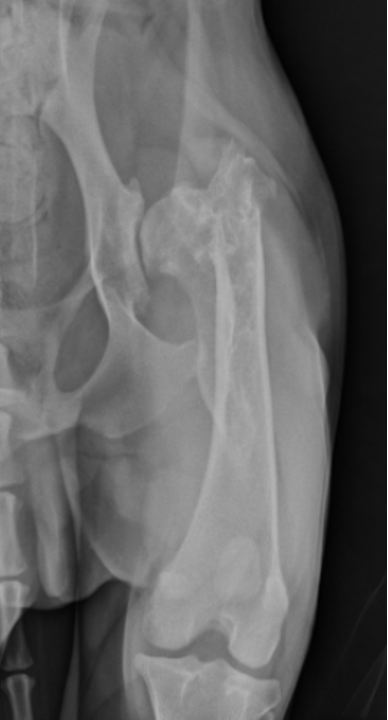

hip dysplasia signalment

large breed dogs

bilateral - inherited

flattened acetabulum, bad femoral head coverage, osteophytes along rim, morgans line

hip dysplasia

morgans line - early sign of DJD